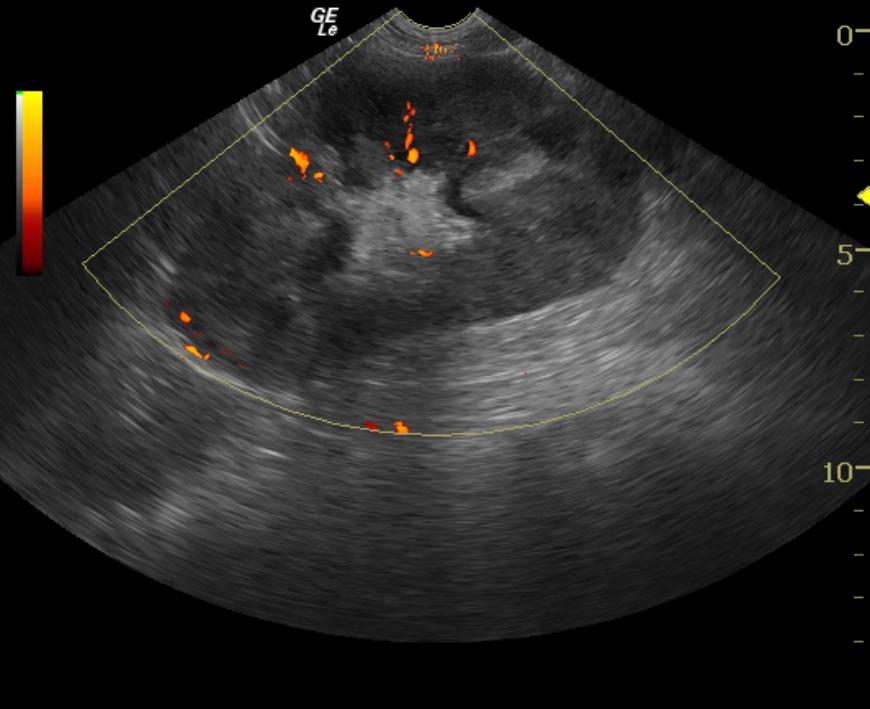

A 6-year-old female spayed Labrador Retriever dog was presented with upper gastrointestinal signs of 2 days’ duration. The patient was treated with antibiotics, gastroprotectants, and anti-emetics. Upper gastrointestinal signs continued despite the treatments, and the dog developed excessive panting and shaking. Blood chemistry revealed azotemia, hyperalbuminemia, and hyperphosphatemia. CBC revealed elevated hematocrit and elevated hemoglobin. Abdominal radiographs did not reveal any abnormalities. The dog was treated with IV fluids, however her azotemia continued to worsen despite treatment.